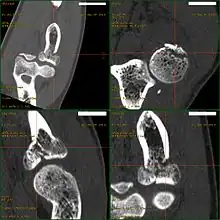

CT scan demonstrating the Mason type III radial head fracture

CT scan showing a radial head fracture

Radial head fractures are diagnosed from an assessment and diagnostic imaging. Assessment may include pain or tenderness at the radial head, bruising, swelling, and a limited range of motion of the elbow.[7] Diagnostic imaging may include ultrasound, plain X-ray, CT scan, and magnetic resonance imaging (MRI).[7][8] A fat pad sign may be present on diagnostic imaging and may indicate a radial head fracture.[9]